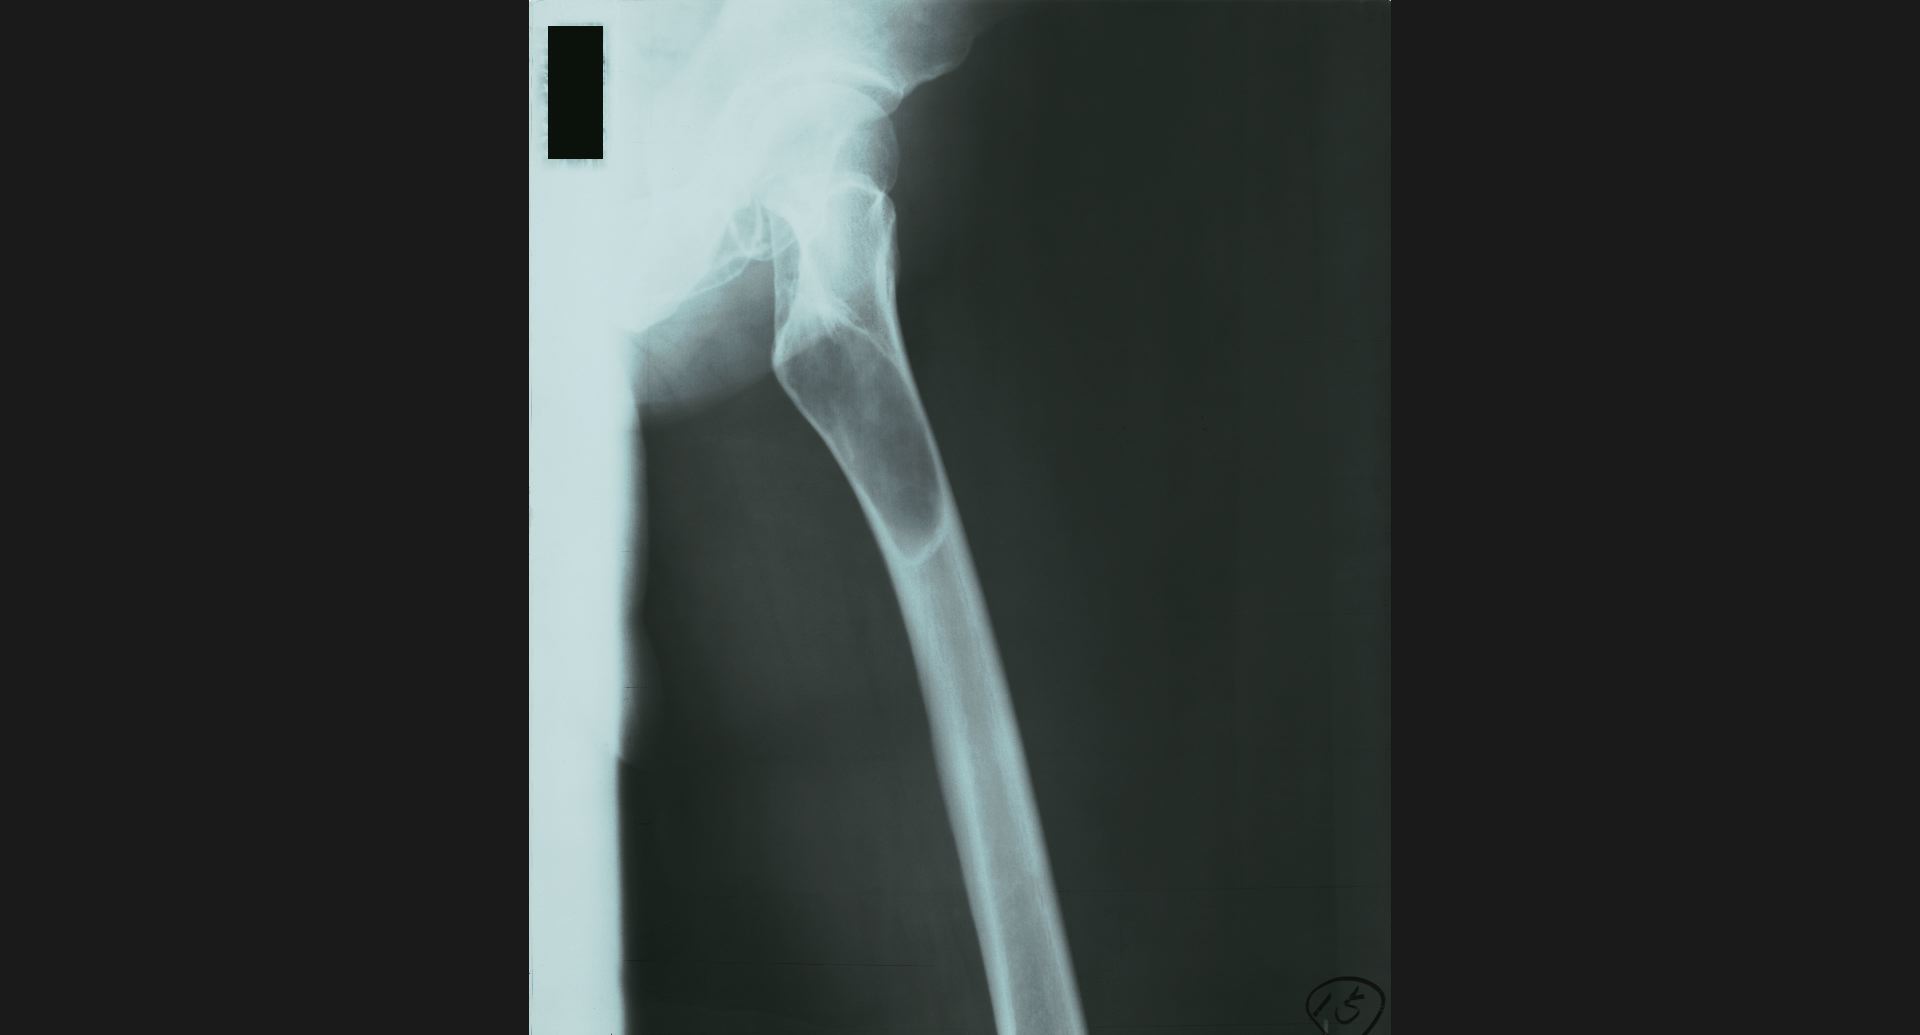

fig.15(55KB)

:Fibrous dysplasia骨頭のtrabeculation。病変部。